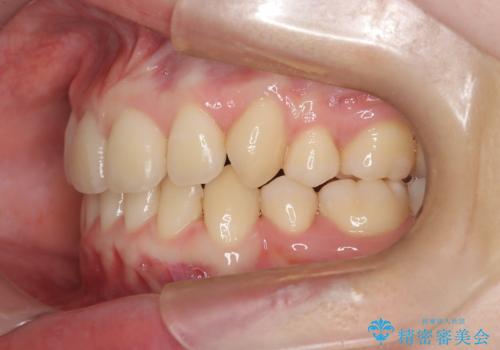

- 八重歯が気になるとのことでご相談いただきました。診察すると、歯列のスペース不足により犬歯が外側に飛び出している状態でした。このままでは歯を並べるスペースが足りないため、抜歯矯正が必要と判断。治療は目立ちにくいインビザラインで行い、歯の移動をサポートするためにゴムかけ(顎間ゴム)を併用する計画を立てました。

抜歯後、インビザラインを用いて少しずつ歯を移動させ、空いたスペースに八重歯を整列させました。さらに、ゴムかけを行うことで上下の噛み合わせを適切に調整。治療後は、八重歯が綺麗に並び、バランスの取れた歯並びと自然な噛み合わせを実現できました。患者様にも「仕上がりがとても綺麗で、口元の印象が変わった」とご満足いただきました。